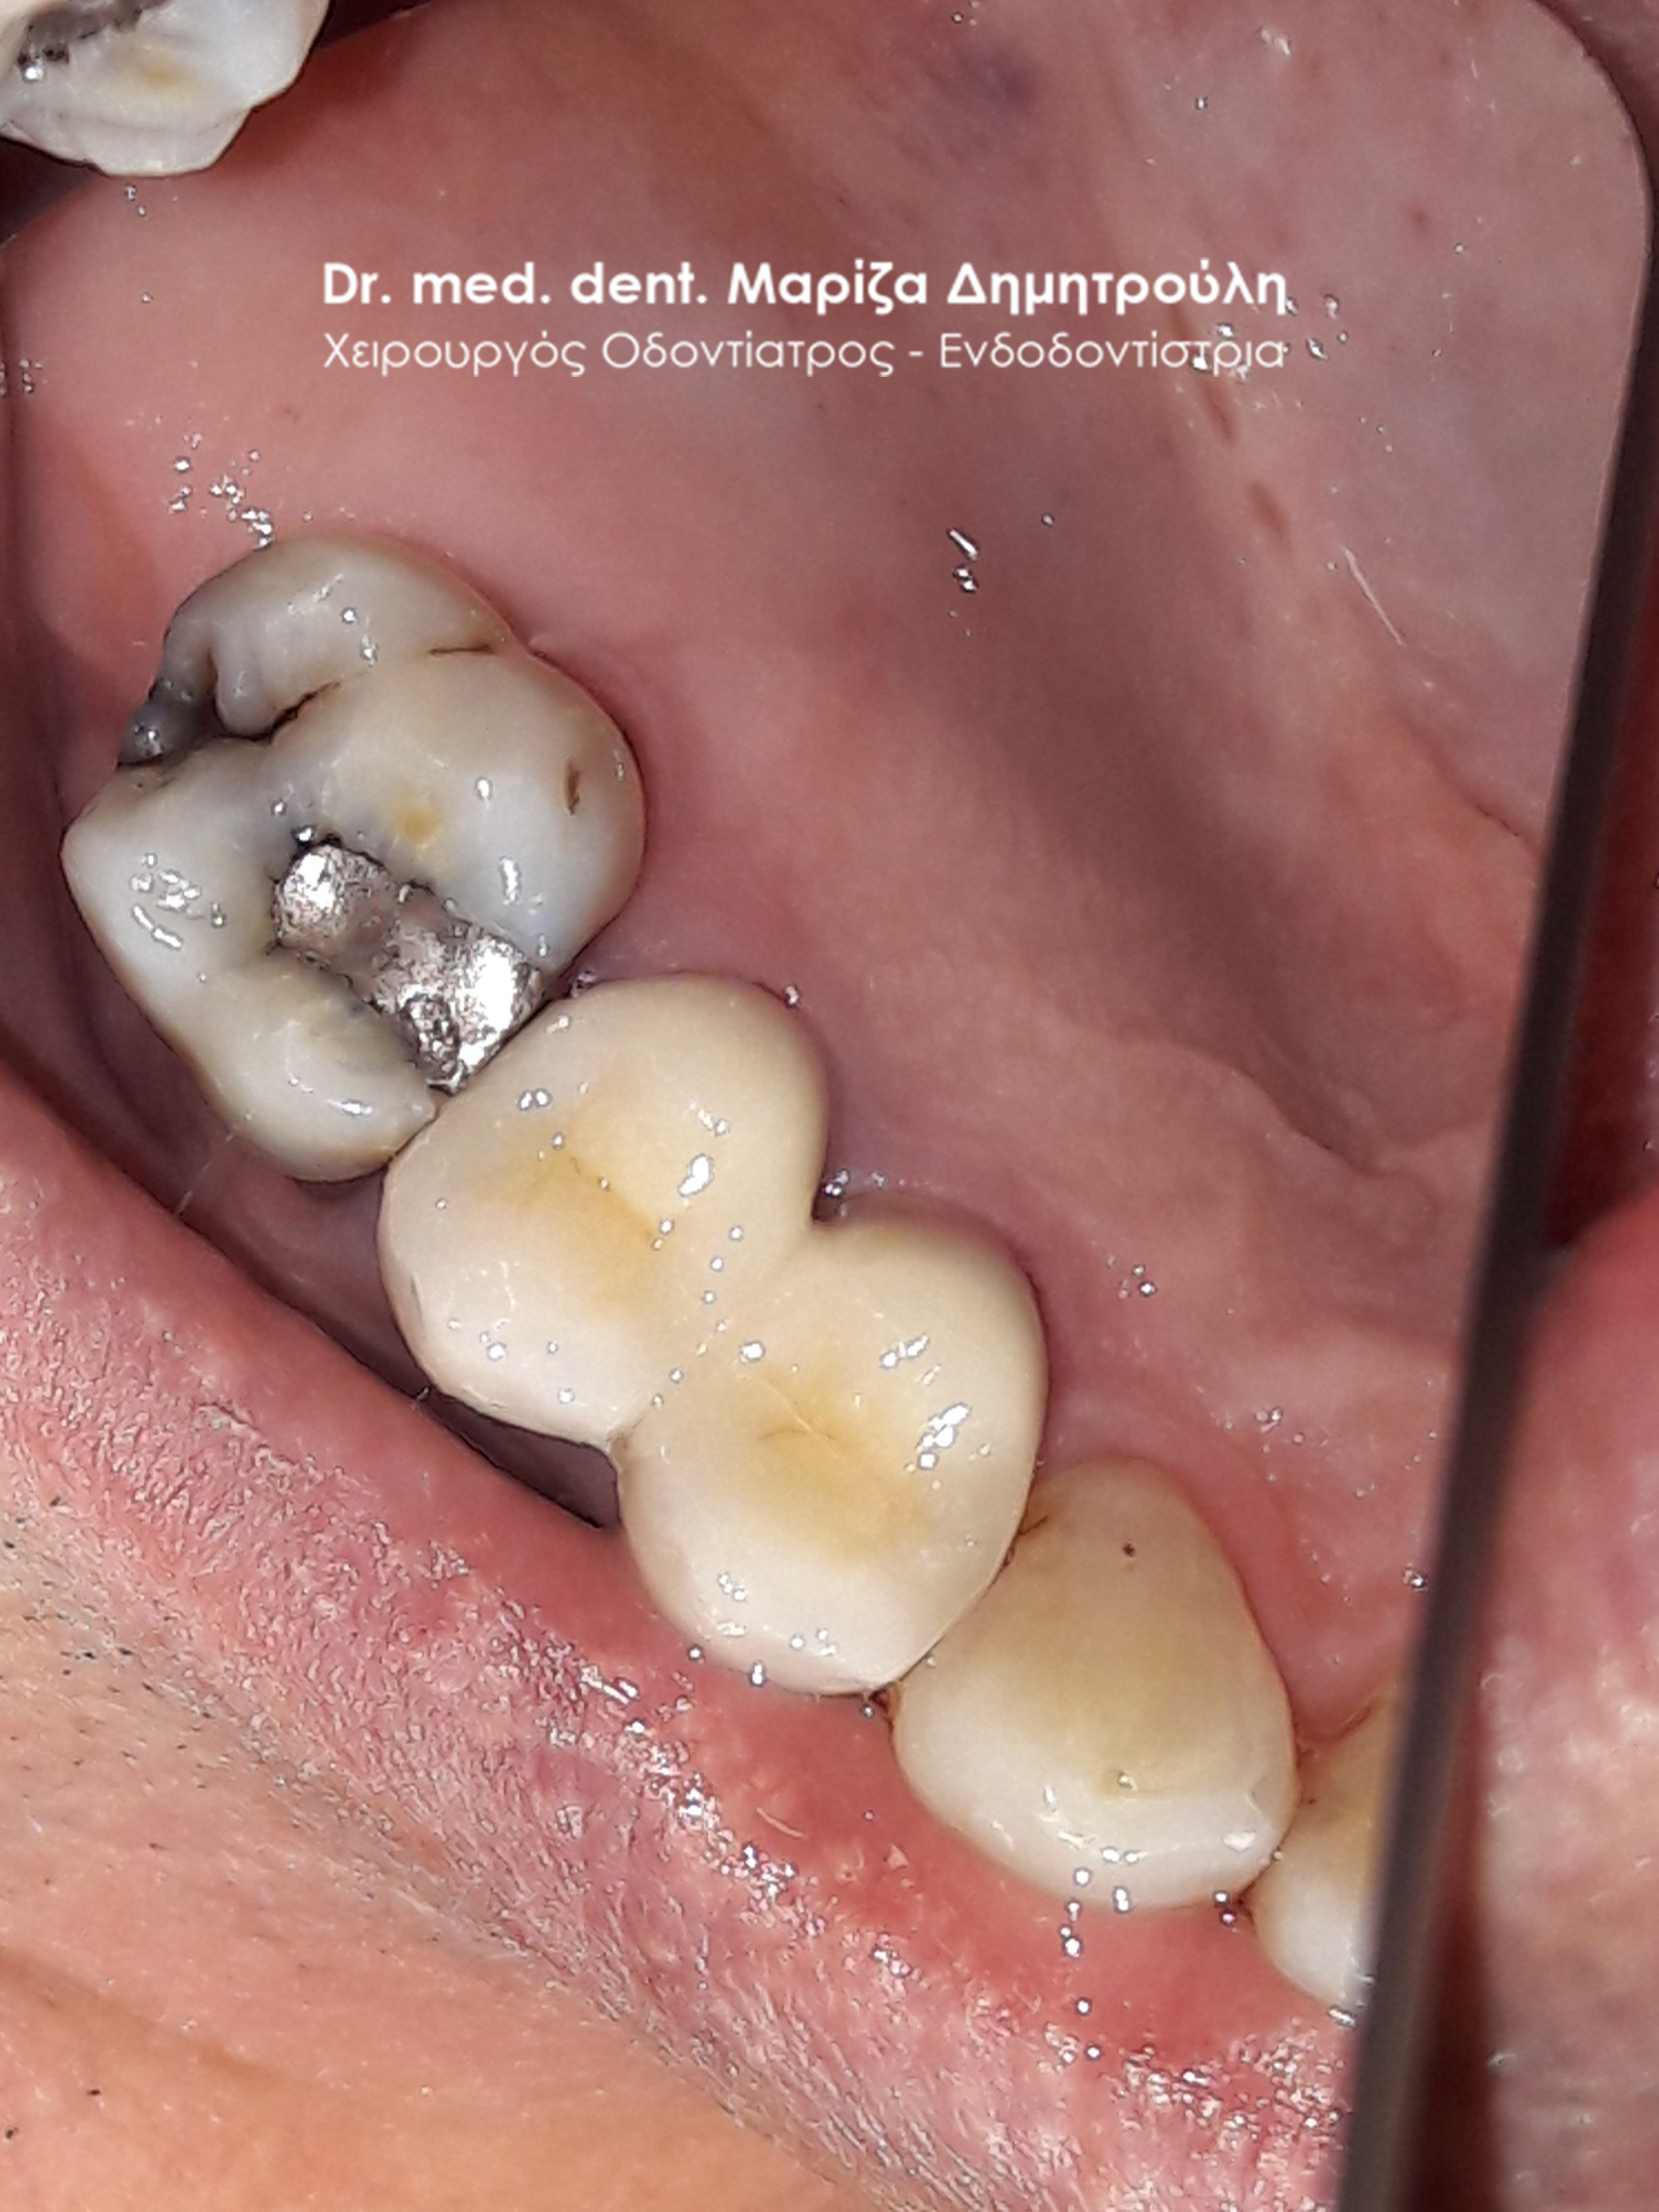

Περιστατικό – Ολοκεραμική στεφάνη / θήκη ζιρκονίου στην αριστερή πλευρά της κάτω γνάθου

Η ασθενής είχε ένα παλιό μαύρο σφράγισμα αμαλγάματος το οποίο την πονούσε. Μετά την κλινική και ακτινογραφική εξέταση του δοντιού αποφασίστηκε η αφαίρεση του παλιού σφραγίσματος, η νέα ανασύσταση και η κάλυψη του δοντιού με ολοκεραμική θήκη δοντιού, καθώς το οδοντικό έλλειμμα ήταν μεγάλο.

Αρχική κλινική εικόνα του δοντιού με το παλιό μαύρο σφράγισμα αμαλγάματος

Τελική εικόνα του δοντιού με τη νέα ολοκεραμική στεφάνη